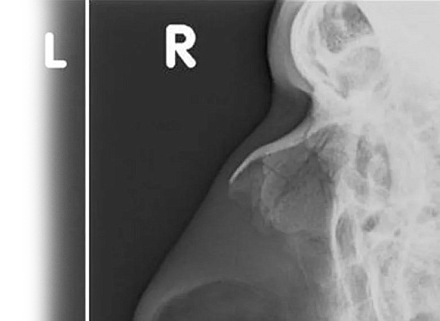

Рентгенография костей носа – важный метод прицельного исследования для оценки состояния костей носа.

Диагностическая услуга выполняется в одной проекции.

• травма лицевой области и носа;

• для исключения перелома костей носа;